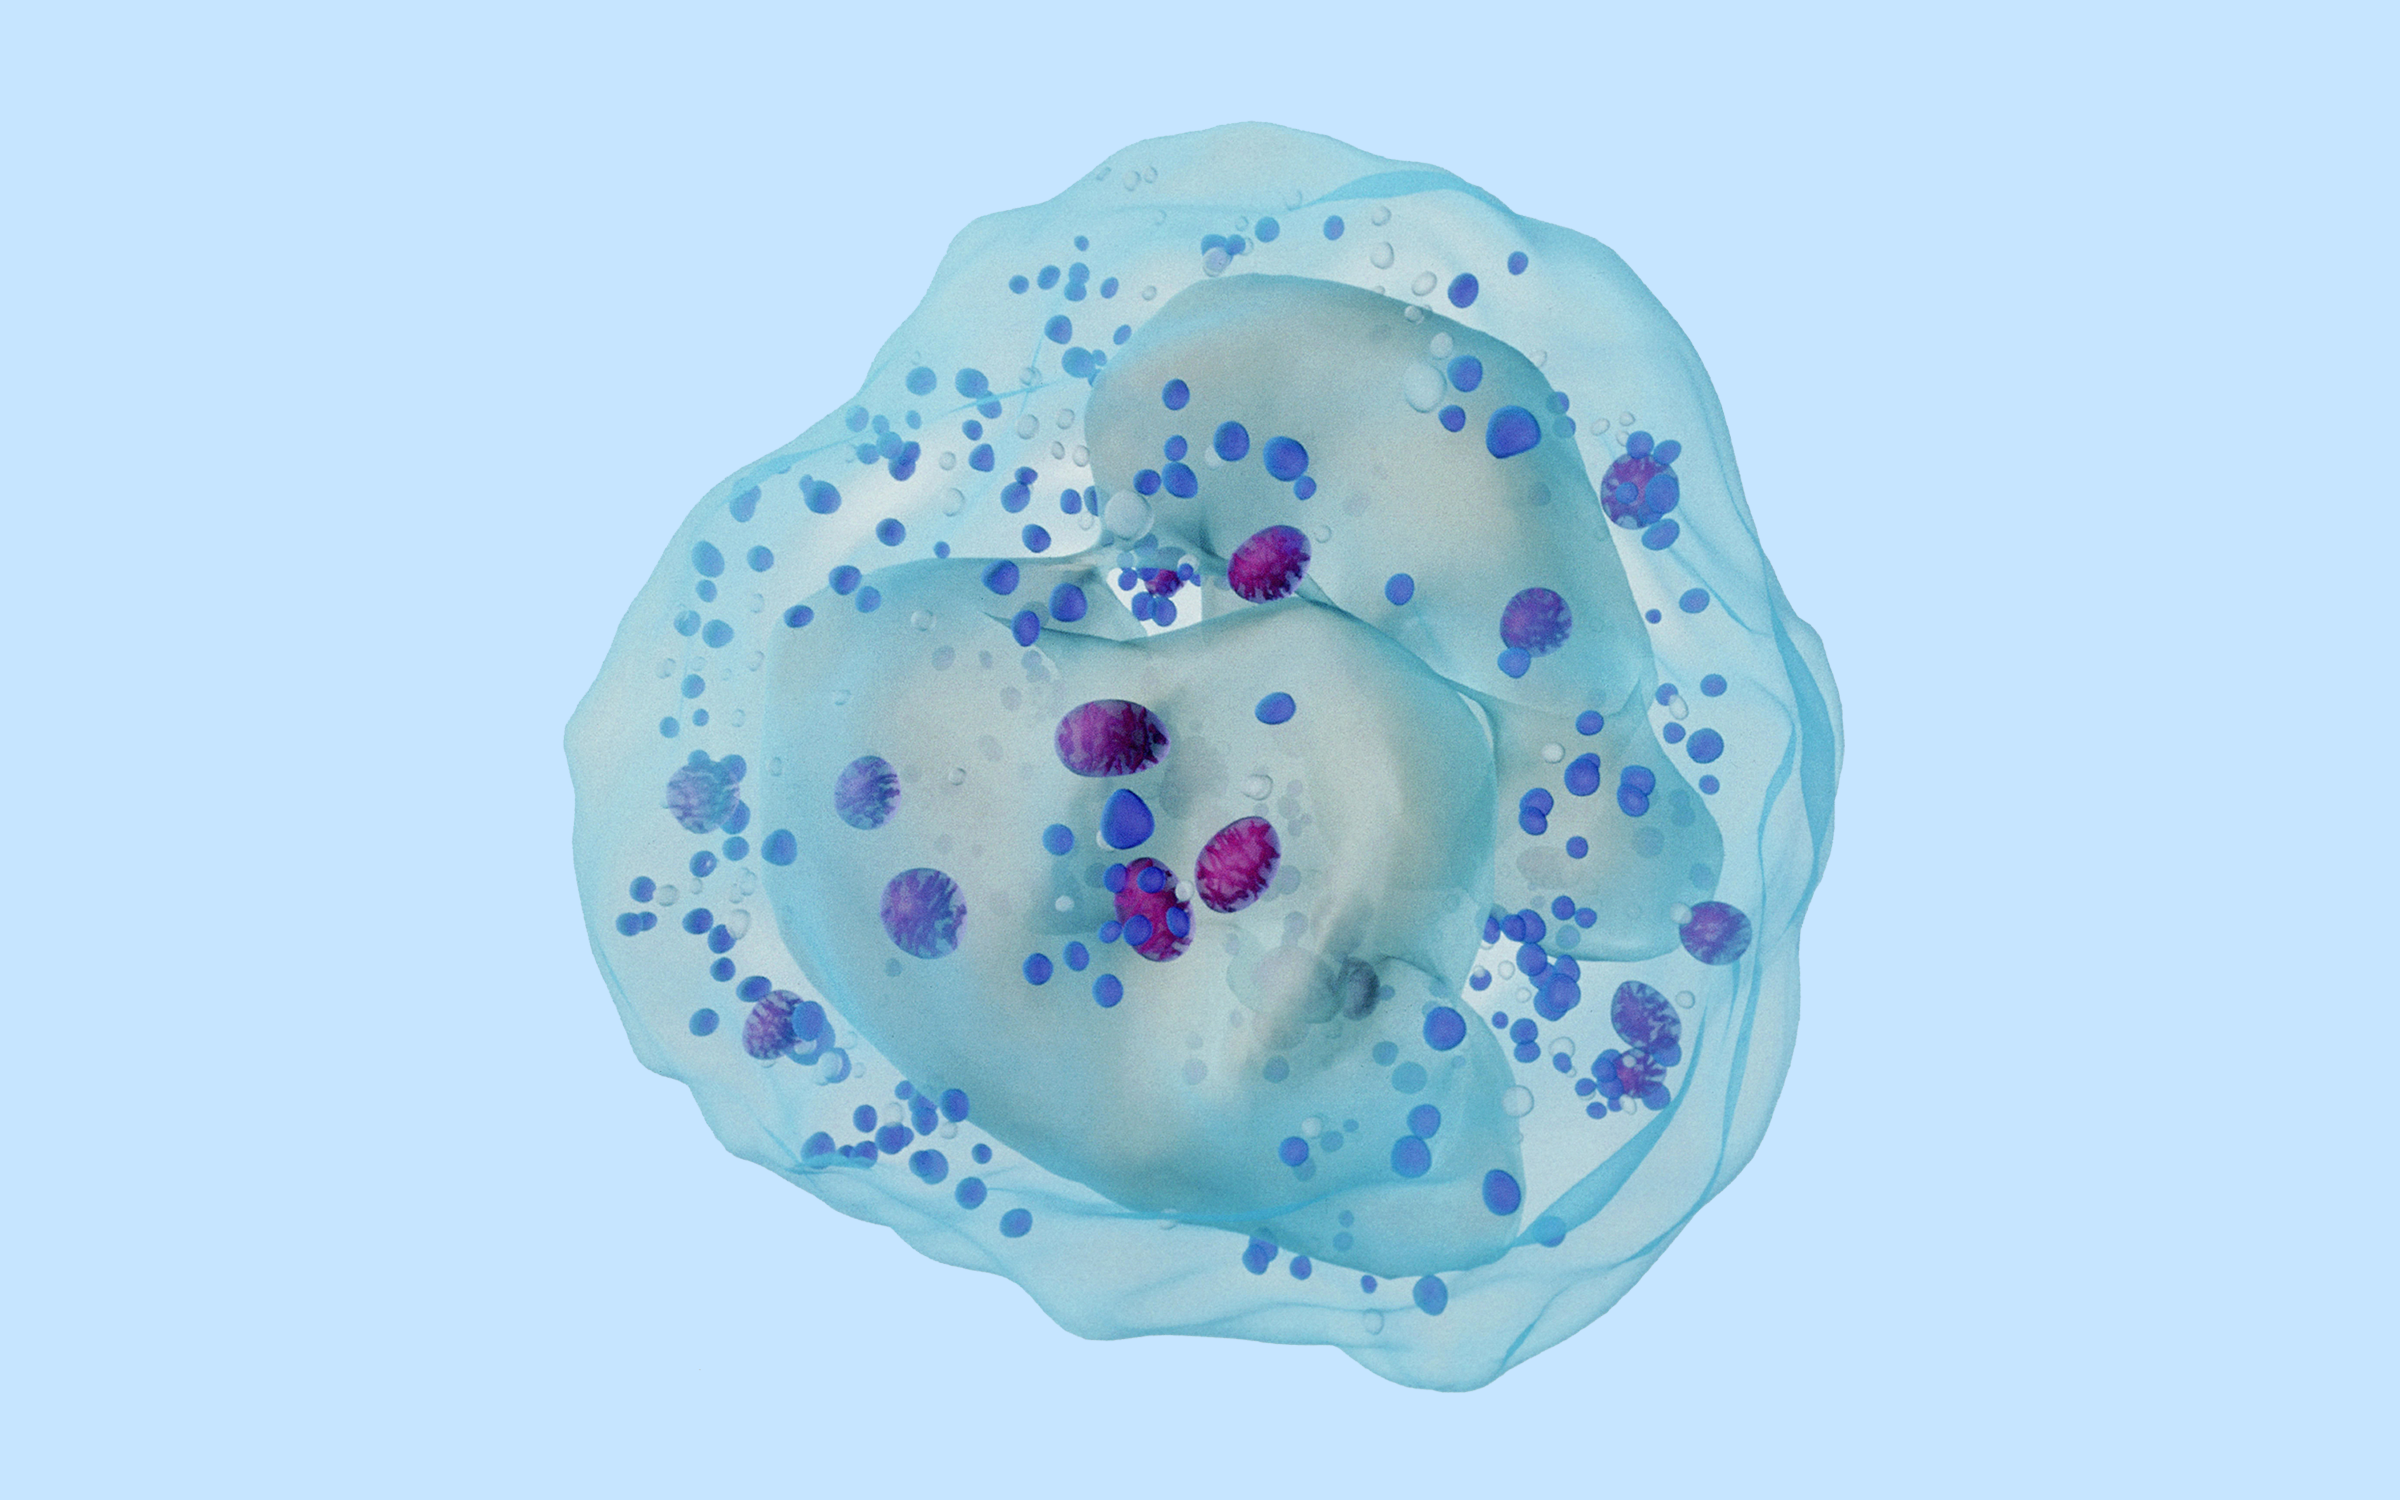

招募复发/难治性B细胞淋巴瘤患者 | EGFR/BTK双靶点抑制剂

进行中适应症:复发/难治性B细胞淋巴瘤

克耐替尼治疗复发/难治性B细胞淋巴瘤的探索性临床研究